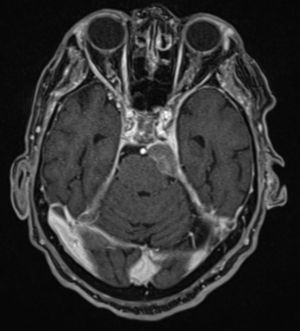

Paciente de 73 años con adenocarcinoma de próstata estadio iv, desde hace diecinueve meses, por afectación ósea múltiple y hepática única, tratado con radioterapia pélvica, hormonoterapia, y dos líneas de quimioterapia. Como antecedentes de interés destacan enfermedad de Parkinson, diabetes mellitus tipo 2, hipertensión arterial y hábito tabáquico. Presenta, desde hace doce meses, disfunción del nervio hipogloso mayor izquierdo que se puso en relación con una lesión ósea en la base del cráneo por la que recibió radioterapia paliativa. Hace siete meses comenzó con diplopia por parálisis del músculo recto lateral del ojo izquierdo atribuida a neurotoxicidad por los tratamientos recibidos. Meses después presentó también paresia del músculo recto lateral del ojo contralateral. Acude a revisión por deterioro general. En la consulta se aprecia discreta desviación de la comisura bucal izquierda. Una exploración más detallada permite detectar hipoacusia ipsilateral, disfagia y desviación lateral de la cabeza hacia la izquierda, de nueva aparición. Se desestima la realización de una punción lumbar diagnóstica por deseo del paciente de limitar la realización de maniobras invasivas. Se realiza una RM cerebral de la que se obtienen las imágenes que se presentan (figs. 1 y 2).

En la RM cerebral se objetivó una masa dural que ocupaba el ángulo pontocerebeloso izquierdo, extendiéndose cranealmente por la vertiente izquierda de la cisterna prepontina hasta el seno cavernoso de ese lado, con dudosa infiltración del tronco encefálico. Se descartaron lesiones isquémicas de evolución aguda y/o signos de carcinomatosis leptomeníngea. Ocupación mastoidea izquierda ya conocida sin cambios respecto a exploraciones previas.